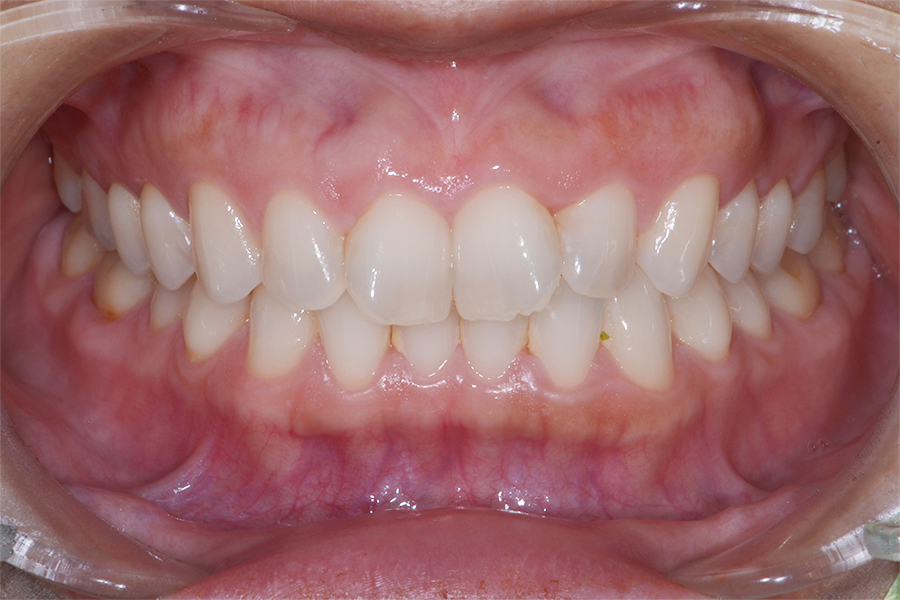

【20代女性】

真ん中二本のねじれを

引っ込めたい

【矯正歯科治療】

- 担当医

- 三留先生

- 主訴

- 真ん中二本のねじれを引っ込めたい

- 期間

- 7か月

- 費用

- 治療費20万(別途調整料)

- 治療内容

- 上顎ラビアル矯正(表側矯正)

- 治療に伴うリスク

- 後戻り